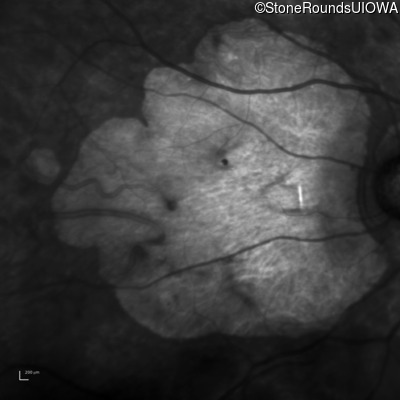

Age at visit: 43 years

OD OS